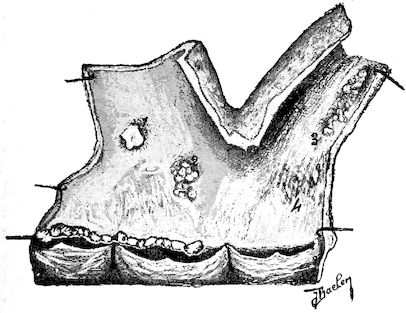

Fig. 8.—Transverse section through the middle region of the face in a pig suffering from osseous cachexia.

18In the final stages, the bones may be cut with a knife, and a time arrives when bony tissue seems completely to have disappeared; thus, as shown in Fig. 8 herewith, it was possible to cut the entire head of a pig into thin slices without the slightest difficulty. All parts of the head had been affected by the softening change.